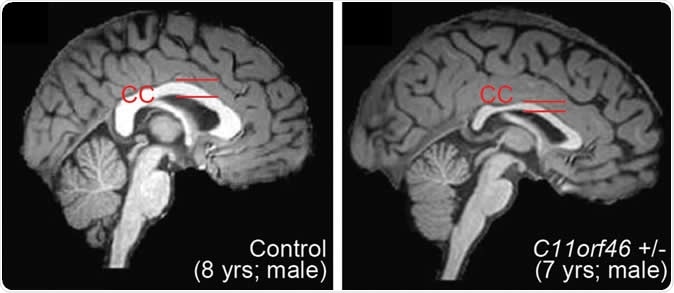

Healthy human brain (left) and brain with WAGR syndrome, in which the corpus callosum is thinner and misformed. Image Credit: Nature Communications

The gene they corrected is called C11orf46 and is crucial for controlling the development of the brain. It is responsible for the production of a nuclear protein that regulates certain important proteins that are capable of directing the newly forming long nerve fibers growing out of the developing nerve cells in the right orientation. These direction-sensing proteins help the white matter fibers to bundle together and form the large nerve trunk that traverses the space between the two hemispheres. This is the corpus callosum, and when it is improperly formed, the individual may be disabled, develop autism or another developmental disorder of the brain. Defects in the C11orf46 gene are linked to hypoplasia or poor development of the corpus callosum.